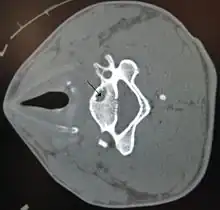

| A bone cyst in the vertebra of the neck as seen on CT | |

On CT scans, bone cysts that have a radiodensity of 20 Hounsfield units (HU) or less, and are osteolytic, tend to be aneurysmal bone cysts.[1]

In contrast, intraosseous lipomas have a lower radiodensity of -40 to -60 HU.[2]